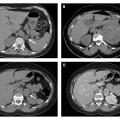

Goutte : aspect en double contour

ARTHROPATHIES A CRISTAUX

Image